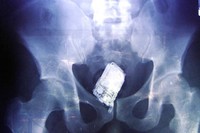

Laki-laki 60 tahun asal Multan, Pakistan mendatangi Nishtar Hospital dengan keluhan yang agak janggal, sejanggal hasil pemindaian dengan sinar X. Sebotol minuman bersoda merek Pepsi terjebak di anusnya, konon dimasukkan secara paksa oleh seorang penjahat yang kepergok akan mencuri 2 ekor sapinya. (Foto: Reuters)